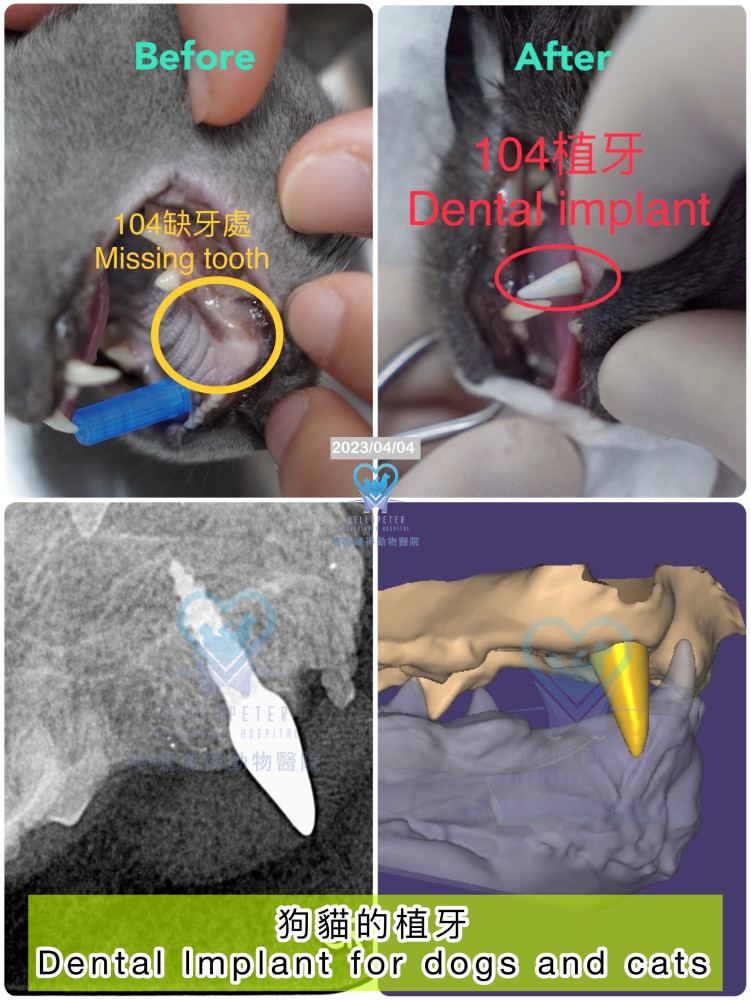

犬上顎104缺牙處與植牙完成後臨床及X光對照影像